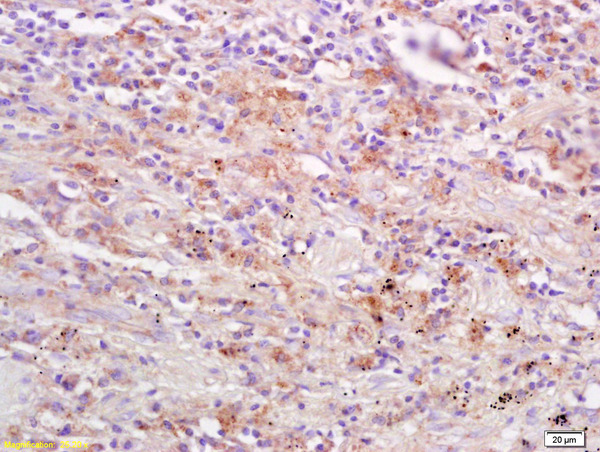

- Main image

- Experimental details

- Formalin-fixed and paraffin embedded human lung carcinoma labeled Anti-DAPK2/DRP1 Polyclonal Antibody, Unconjugated (bs-1713R) at 1:200, followed by conjugation to the secondary antibody and DAB staining

- Sample type

- Human

- Other comments

- Lung